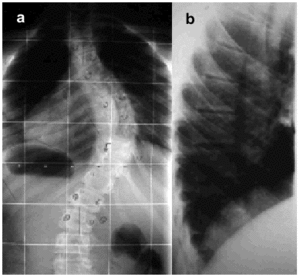

Scoliosis is defined as lateral curvature of the spine with vertebral rotation, meaning that it is a 3-dimensional deformity. Scoliosis leads to thoracic deformity if the spinal alterations occur in that zone (Figure 1).

Figure. 1. Thoracoabdominal x-ray showing posteroanterior (a) and lateral (b) views of a spine with scoliosis.